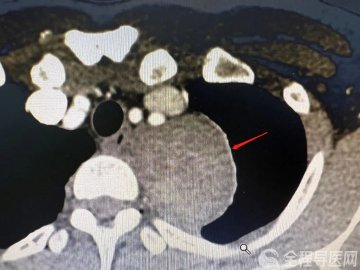

因为患者还是个孩子,无法行常规妇科检查。完善了相关检查,提示其附件区有一个直径约10cm的混合回声包块,考虑畸胎瘤。朱彦玲根据患者反复腹痛且能自然缓解的特点,考虑肿瘤发生了扭转。

畸胎瘤